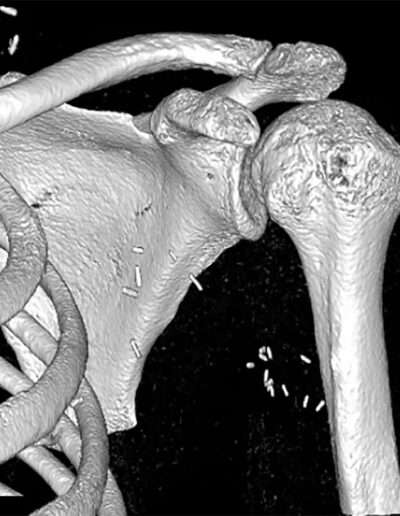

• 09/2023: Motorcycle accident → Brachial plexus injury (C5–C7)

• 3. BUT no glenohumeral active mobility and stability → NON-functional shoulder → Impossible use of the hand

Constant: 21